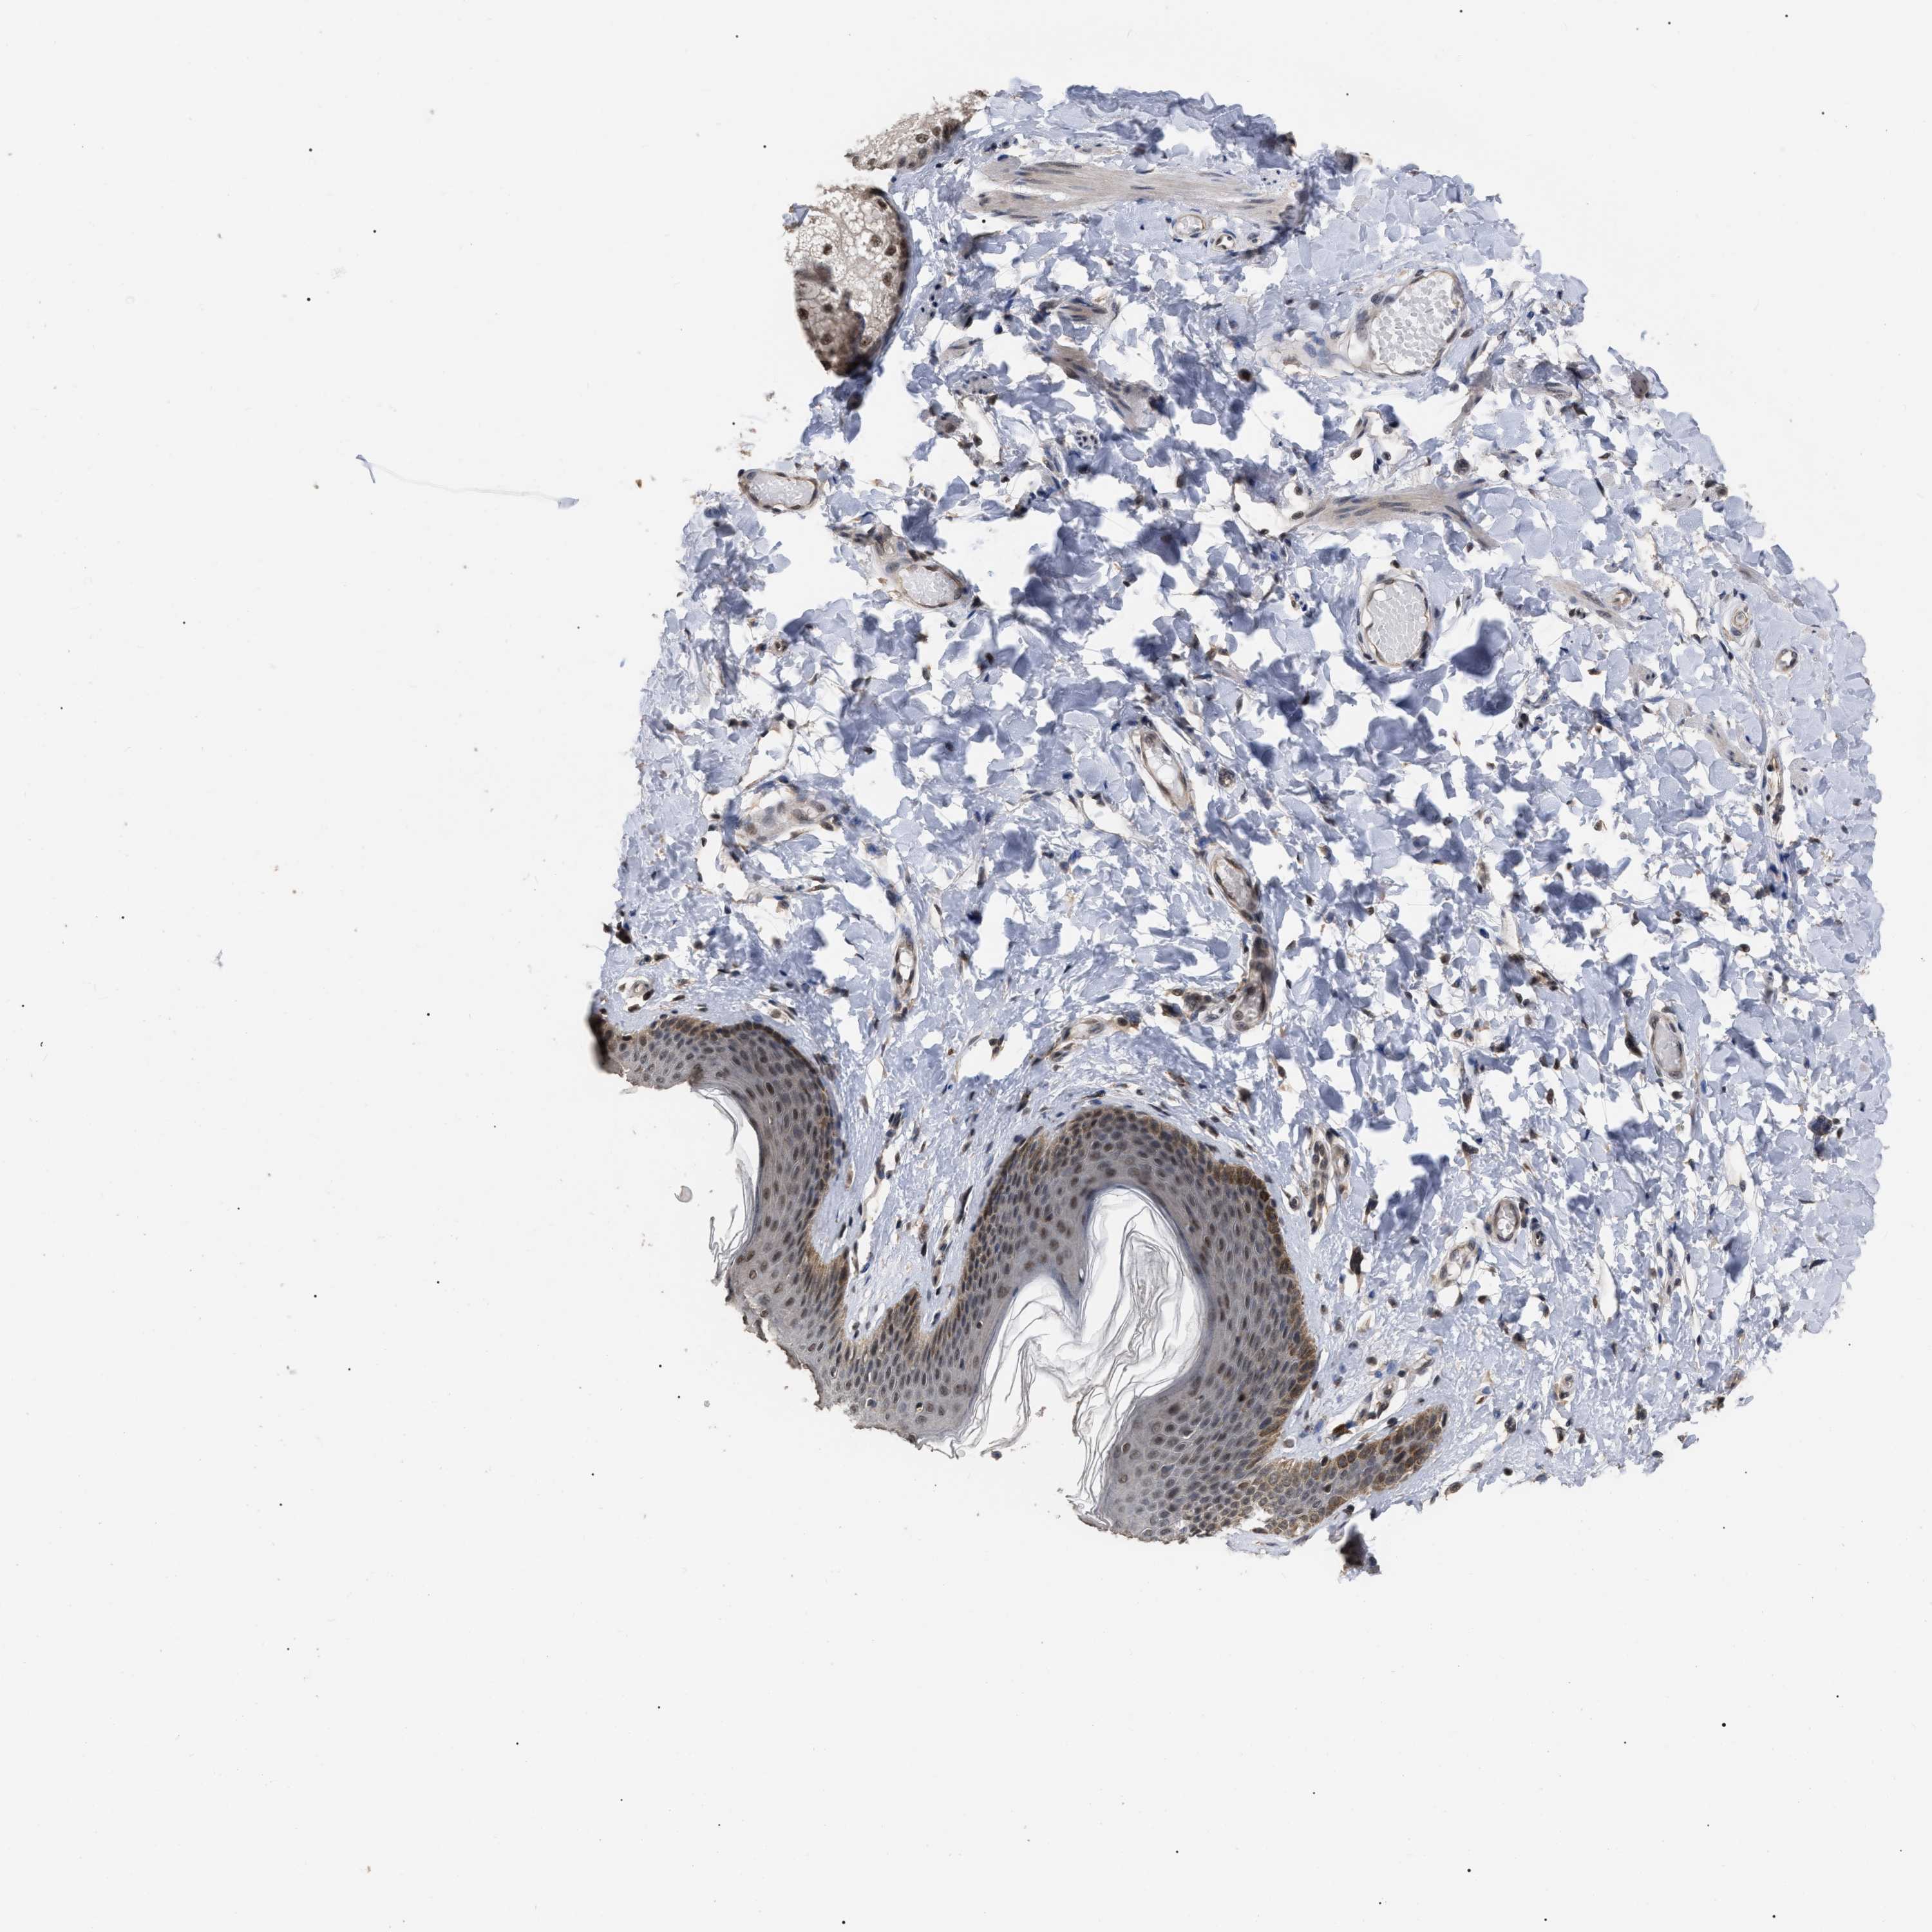

SKIN 1 - Antibody stainingi

Antibody staining in the annotated cell types in the current human tissue is reported as not detected, low, medium, or high, based on conventional immunohistochemistry profiling in selected tissues. This score is based on the combination of the staining intensity and fraction of stained cells.

Each image is clickable and will lead to virtual microscopy that enables deeper exploration of all samples and also displays staining intensity scores, fraction scores and subcellular localization as well as patient and tissue information for each sample.

Antibody CAB019271

Langerhans Not detected

Fibroblasts Not detected

Keratinocytes Low

Melanocytes Not detected

SKIN 2 - Antibody stainingi

Epidermal cells Medium